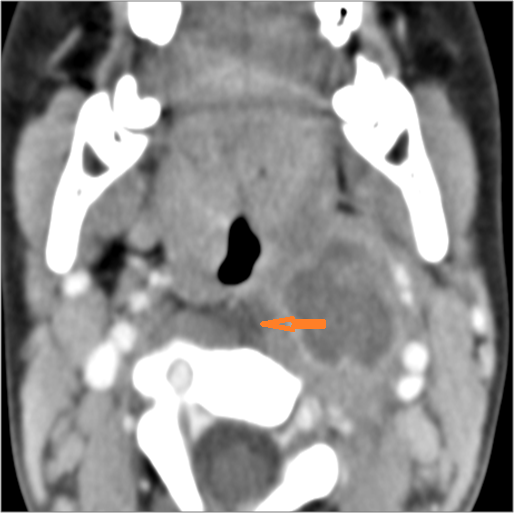

There is abscess within the adjacent deep neck, retropharyngeal and/or prevertebral spaces.